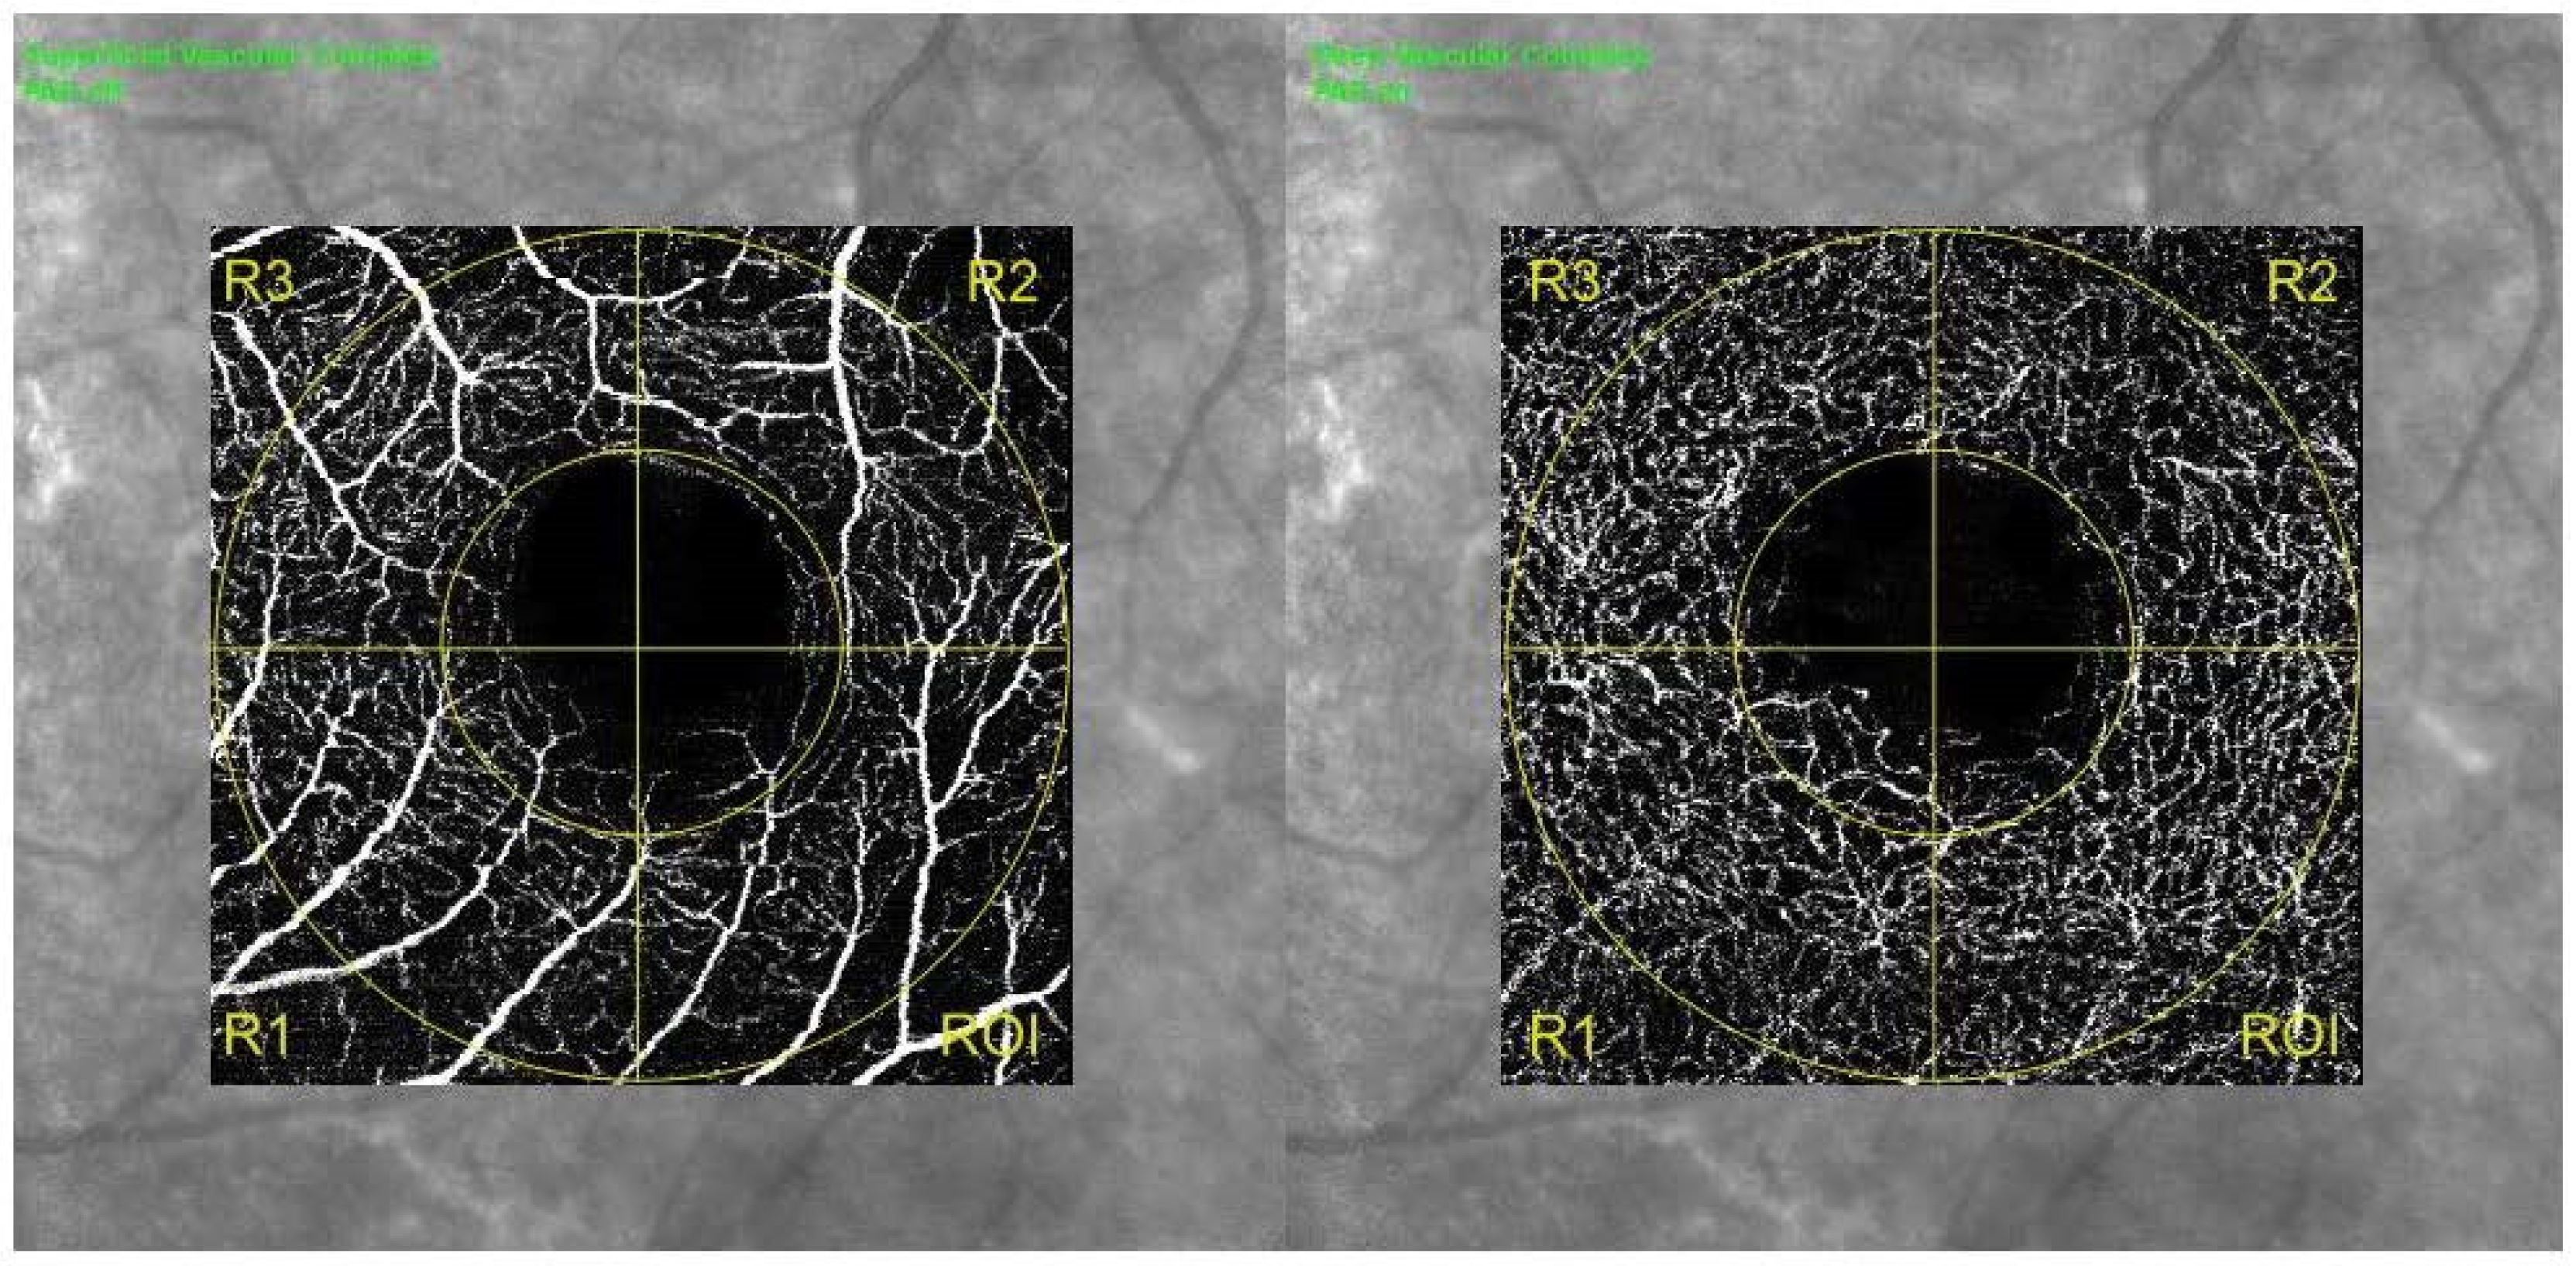

| SCP | CFZ circularity | 0.51 ± 0.07 | 0.60 ± 0.08 | 0.003 |

| CFZ area (mm2) | 0.45 ± 0.11 | 0.40 ± 0.12 | 0.036 | |

| CFZ perimeter (mm) | 3.32 (0.36) | 2.89 (0.24) | 0.041 | |

| Foveal VD (%) | 16.35 ± 1.13 | 20.42 ± 1.78 | 0.012 | |

| Foveal PD (%) | 13.85 (1.18) | 18.98 (1.6) | 0.007 | |

| Parafoveal VD (%) | 0.44 ± 2.36 | 0.47 ± 2.13 | 0.071 | |

| Parafoveal PD (%) | 0.36 (2.77) | 0.43 (2.83) | 0.009 | |